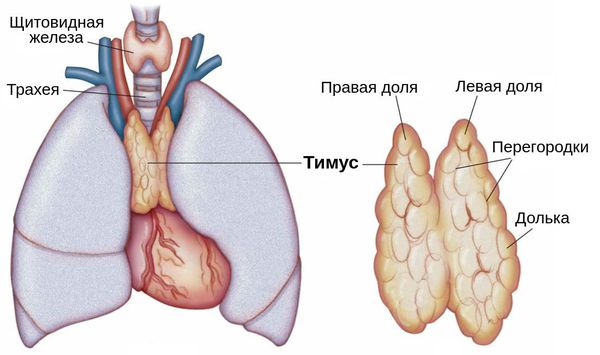

Фотографии вилочковой железы тимуса: структура и функции